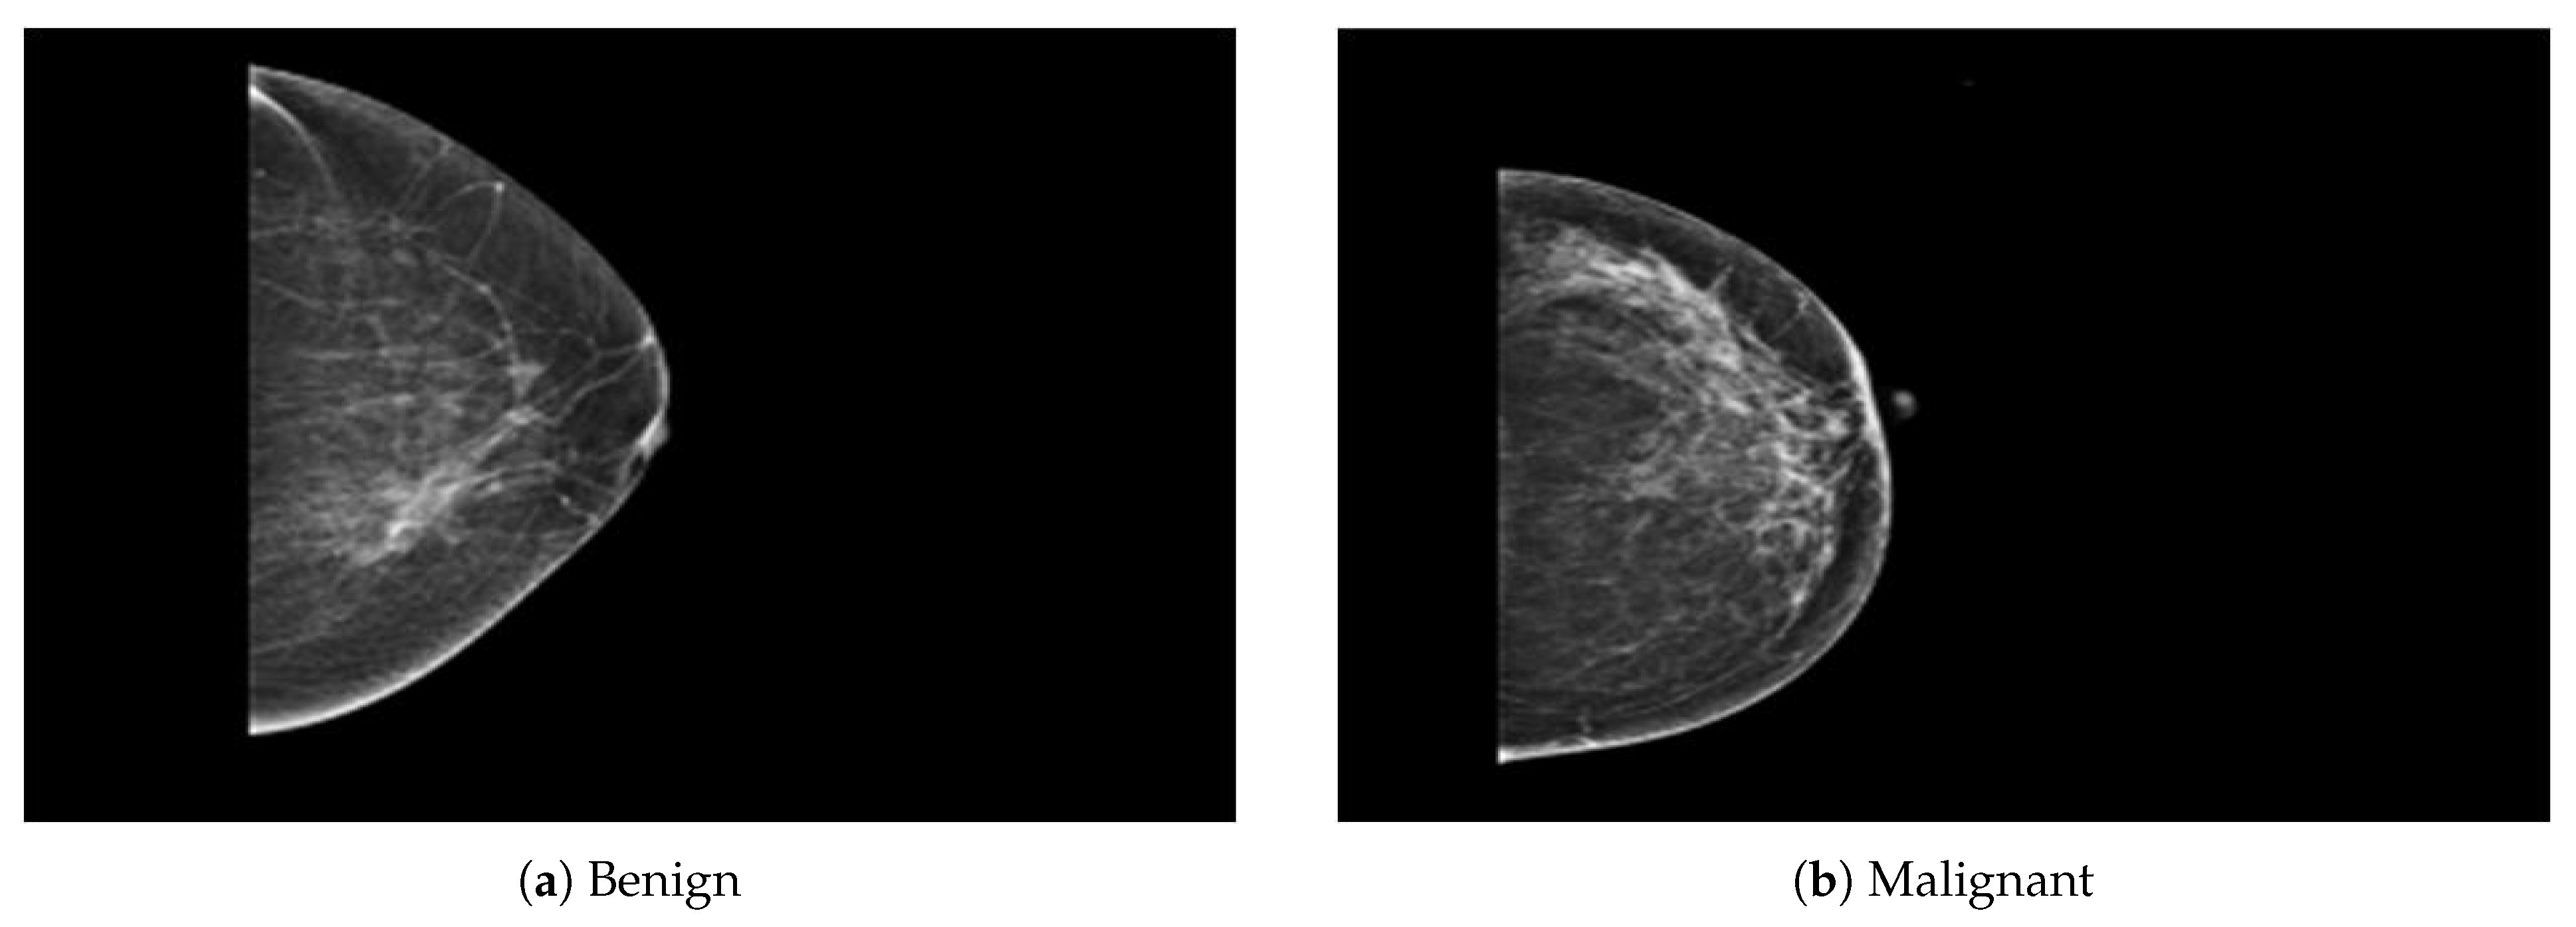

The dataset was collected from a local (PINUM) hospital [51] in Pakistan, with the approval of the Diagnostic Imaging Nuclear Medicine and Radiology Research and Development Committee. A total of 289 patients were manually labeled by the expert radiologist using the initial mammogram reports generated by the mammography machine and included ages between 32 and 73 with a mean age of 48.5 years. The radiologist team consisted of two members, one being a senior radiologist and physicist holding a PhD degree in nuclear medicine with 10 years of experience and the second being a junior radiologist with a Master’s degree in radiology. The dataset was first evaluated with the proposed method to increase the sensitivity of breast cancer prediction using a fully automated CAD system. The dataset included 577 original images consisting of 425 benign and 152 malignant images with both MLO (mediolateral-oblique) and CC (craniocaudal) views at a resolution of 4096 × 2047, as shown in Figure 2. Each CC and MLO view image had a focal length of 35 mm with a 96 dpi resolution along the horizontal and vertical axis. The mammography exam of the PINUM dataset was acquired with Hologic 2D, 3D mammography. Data augmentation techniques were employed on the PINUM dataset to increase the size to regularize and train the deep convolutional neural network. Each mammogram image was rotated at four angles, obtaining five images, including one original and four rotated images. Moreover, we included another public dataset, the Digital Database for Screening Mammography (DDSM) [52], for the evaluation of our model, which contains 3568 mammogram images (1740 benign, 1828 malignant) from 870 benign and 914 malignant cases, as shown in Figure 3. We split the dataset into 60:20:20, where we used 60% for the training of our model, 20% for cross-validation, and the rest for testing. We used 5-fold cross-validation to test our dataset. A detailed description of the dataset is given in Table 1.

Figure 2. An example of breast mammogram images from the PINUM dataset. (a) The benign image. (b) The malignant image. The images were labeled by the expert radiologist in the dataset.